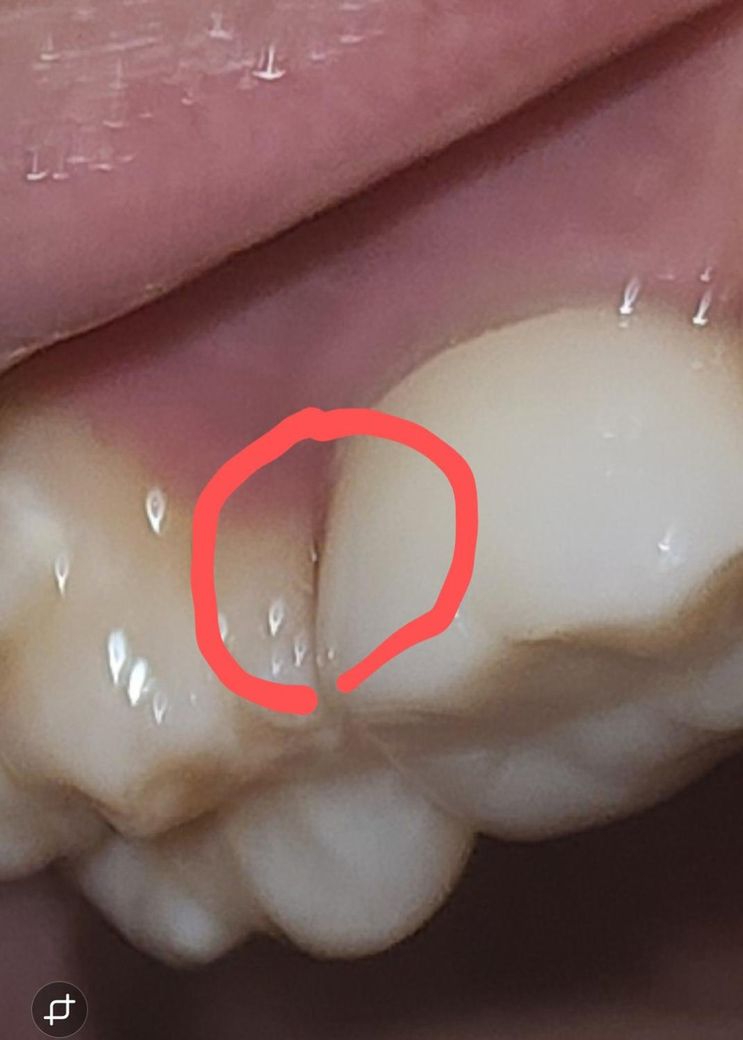

치실사용중에 충치인거같아서 질문드립니다

25년 2월 정도에 스케일링과 치과치료 받았는데 그당시에는 다른 치아에는 충치가 없다고 하셨어요 근데 오늘 치실 사용중에 보다보나 검은 선 비슷한게 보여서 질문드립니다

• 1번 째 사진